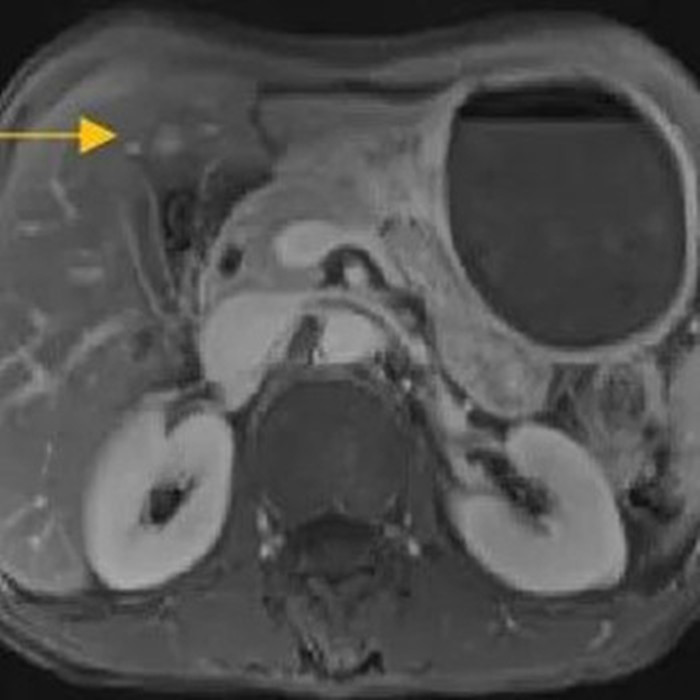

住院后經(jīng)胸腹部CT檢查,提示周先生胃部巨大腫塊穿破胃腔,可能累及到結(jié)腸,同時合并有胃旁淋巴結(jié)轉(zhuǎn)移、肝臟的轉(zhuǎn)移??吹竭@個檢查報告后,周先生和他的愛人一下子就泣不成聲了。

治療前的腹部CT提示胃

治療前肝臟的轉(zhuǎn)移灶